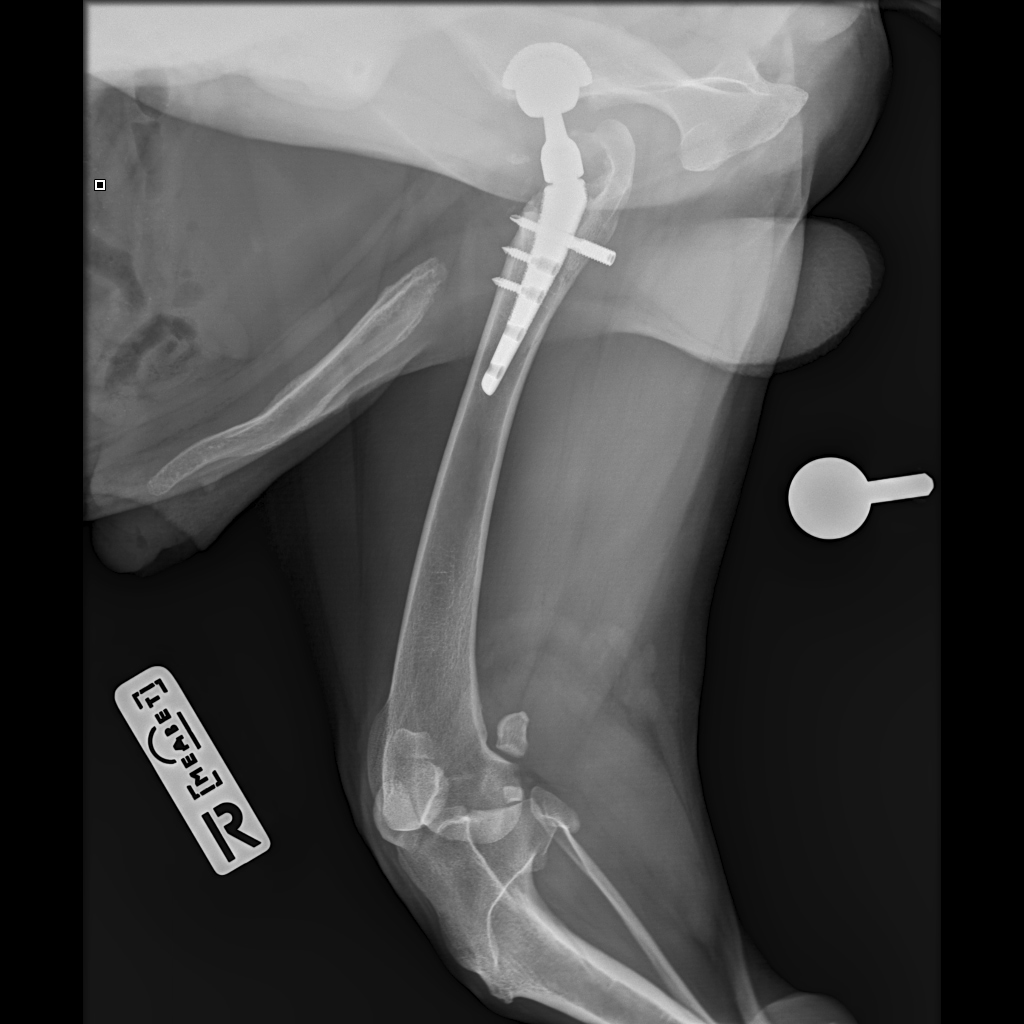

F37B4905-A77F-43B7-A3A7-4AAD9E739F82.jpeg

E6A744CC-768F-480D-8917-7FDAD53F05BD.jpeg

DA1A1524-BA63-434B-95BE-C121F7D5334F.jpeg

4D4A6426-4FE5-4417-ACCB-6DE53B57B90E.jpeg

E358D56E-67BF-4D4C-B3F0-BF8F4089D7A2.jpeg

767DD36C-E2E2-41FB-9CCF-6940421D2BB2.jpeg

701487DA-D6D9-4CE0-B18B-EEB120E78EF2.jpeg

Мы ничего не оплачивали. Все включено.

За время противовоспалительной терапии снизилось воспаление и в левом тазобедренном суставе, но увы, форма головки бедренной кости и состояние шейки бедра , лучше не стали:(((

Операция однозначно нужна.

Снимки столь качественные, что их можно в учебник